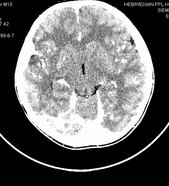

男,10岁,因近来常头痛就诊。先平扫拟诊右侧脉络膜裂囊肿,后薄层(3mm)扫描见此灶与右侧脑室后角相通,且向内几乎与鞍上池相连,并见一血管影沿其走形 (可能是脉络膜前动脉)。1。请教:脉络膜裂或脉络膜裂囊肿与侧脑室颞角或鞍上池相通吗?好像谁说脉络膜裂是脉络膜从外侧裂向侧脑室移行的裂隙。请高手讲讲这点的解剖关系。2。建议:对于老年患者,有丘脑附近特别是右丘脑附近的近似腔隙性梗死灶,临床症状不明显的,应做3mm薄层扫描,看病灶向下是否与侧脑室颞角相连,以免误诊。

薄层强化: